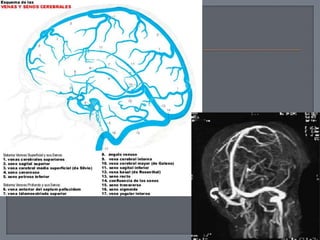

 Los senos son espacios venosos que

drenan la sangre del cerebro y los huesos

del cráneo; se ubican entre dos capas de

duramadre y están recubiertos por

endotelio, que es continuación del que

tapiza a las venas.

 Las venas del encéfalo se caracterizan por

estar dotadas de paredes delgadas y

carecen de válvulas, perforan la

aracnoides y la duramadre y desembocan

en los senos venosos.

 Se agrupan principalmente como:

• Venas cerebrales superiores

• Vena cerebral media superficial

• Venas cerebrales inferiores